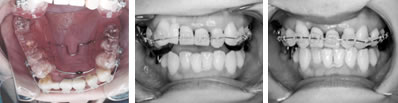

併用した長期経過症例 4歳

治療開始時年齢は6歳半でしたが、永久歯は1本もありませんでした。右上の乳歯Dから左上の乳歯Cまでが反対咬合の状況でした。

レントゲンの検査、家族暦などから骨格的な下顎前突の程度が大きいことがわかりましたので、オトガイ帽装置(チンキャップ)を使用することになりました。

この装置の使用効果についてはさまざまな論拠、発表がありますが、本院では直接的に下顎骨を小さくする効果は無いと考えています。しかしながら、他の装置の使用効果を高めたり、習癖を除去する効果があり、その結果上顎の本来の成長が得られて上下顎の大きさのバランス改善が得られると思われます。少しでも治療を楽しむため色付の装置も用意しています。

普段のかみ合わせのまま下顎を後ろに押し下げようと力をかけた場合、上顎前歯と下顎前歯がぶつかって上顎まで後ろに下げようとする力が働いてしまいます。そこで、チンキャップを使用する場合には前歯の干渉を避けるためにクリアプレートを併用しました。

1年後(7歳半)の口腔内 下顎前歯が抜け替わりましたが、反対咬合の状態です。

装置使用開始4ヶ月目には反対咬合が解消されています。